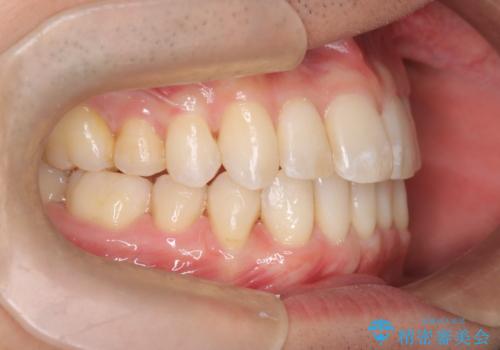

前歯の重なりとガタガタをマウスピースで改善した症例

初診時の歯並びの状態としては、上下ともに前歯部の中等度のがたつきがあり、上の前歯が重なっている状態でした。

また元々下の前歯は1本少なく、歯の本数が少ないことを前提とした矯正治療を行いました。